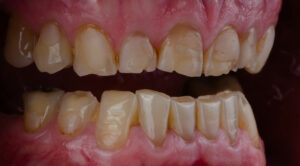

歯の表面のすり減り

歯ぎしりが続くと、歯の表面が異常にすり減ることがあります。

特に犬歯や小臼歯の先端、大臼歯の噛む面が平らになっている場合は、摩耗が起きているサインです。

鏡で確認して、歯の先端が平らになっている、左右で高さが違う、細かい亀裂が見られるといった変化があれば注意が必要です。